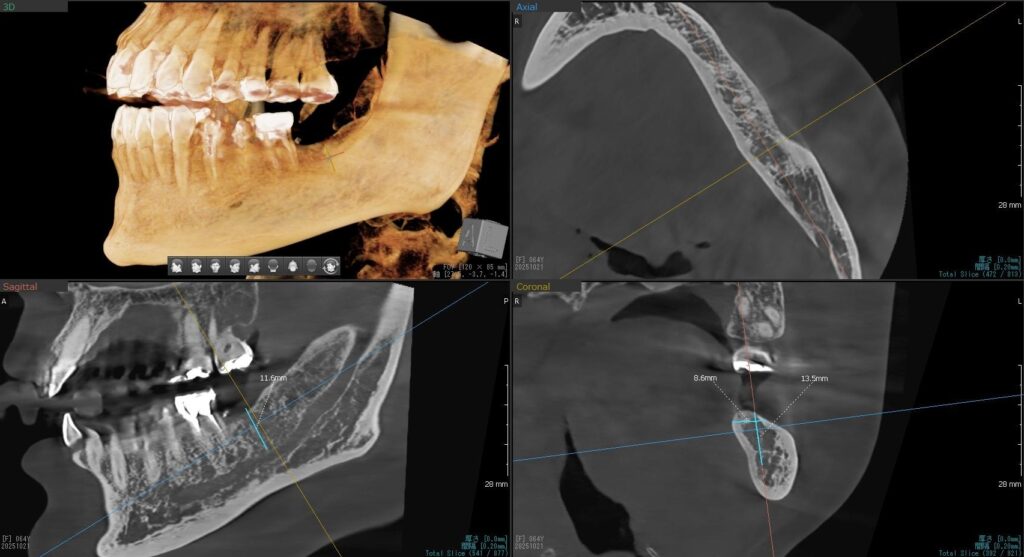

今回の患者様はインプラント植立を希望され、左下7番目、1本の植立が決まりました。

ドリルの先端を細い物から徐々に大きい物に変えながら、植立するインプラント体のネジの部分を除いた胴の部分の太さに合わせた大きさの穴を開けていきます。

開けた穴に、専用道具を使ってネジを締めるように長さ2センチ程のインプラントを骨に埋め込んでいきます。